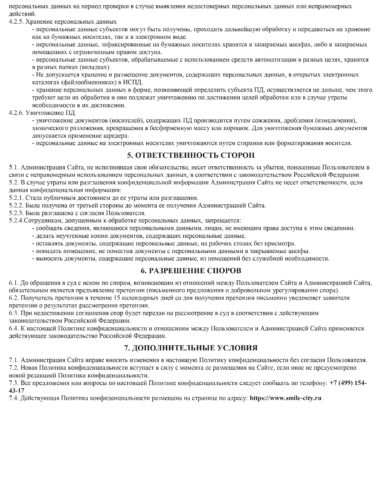

Услуги предоставляются при наличии информированного добровольного согласия Пациента (Законного представителя).

4.5.Ознакомиться и подписать информированное добровольное согласие на медицинское вмешательство, уведомление о последствиях лечения и

рекомендациях.